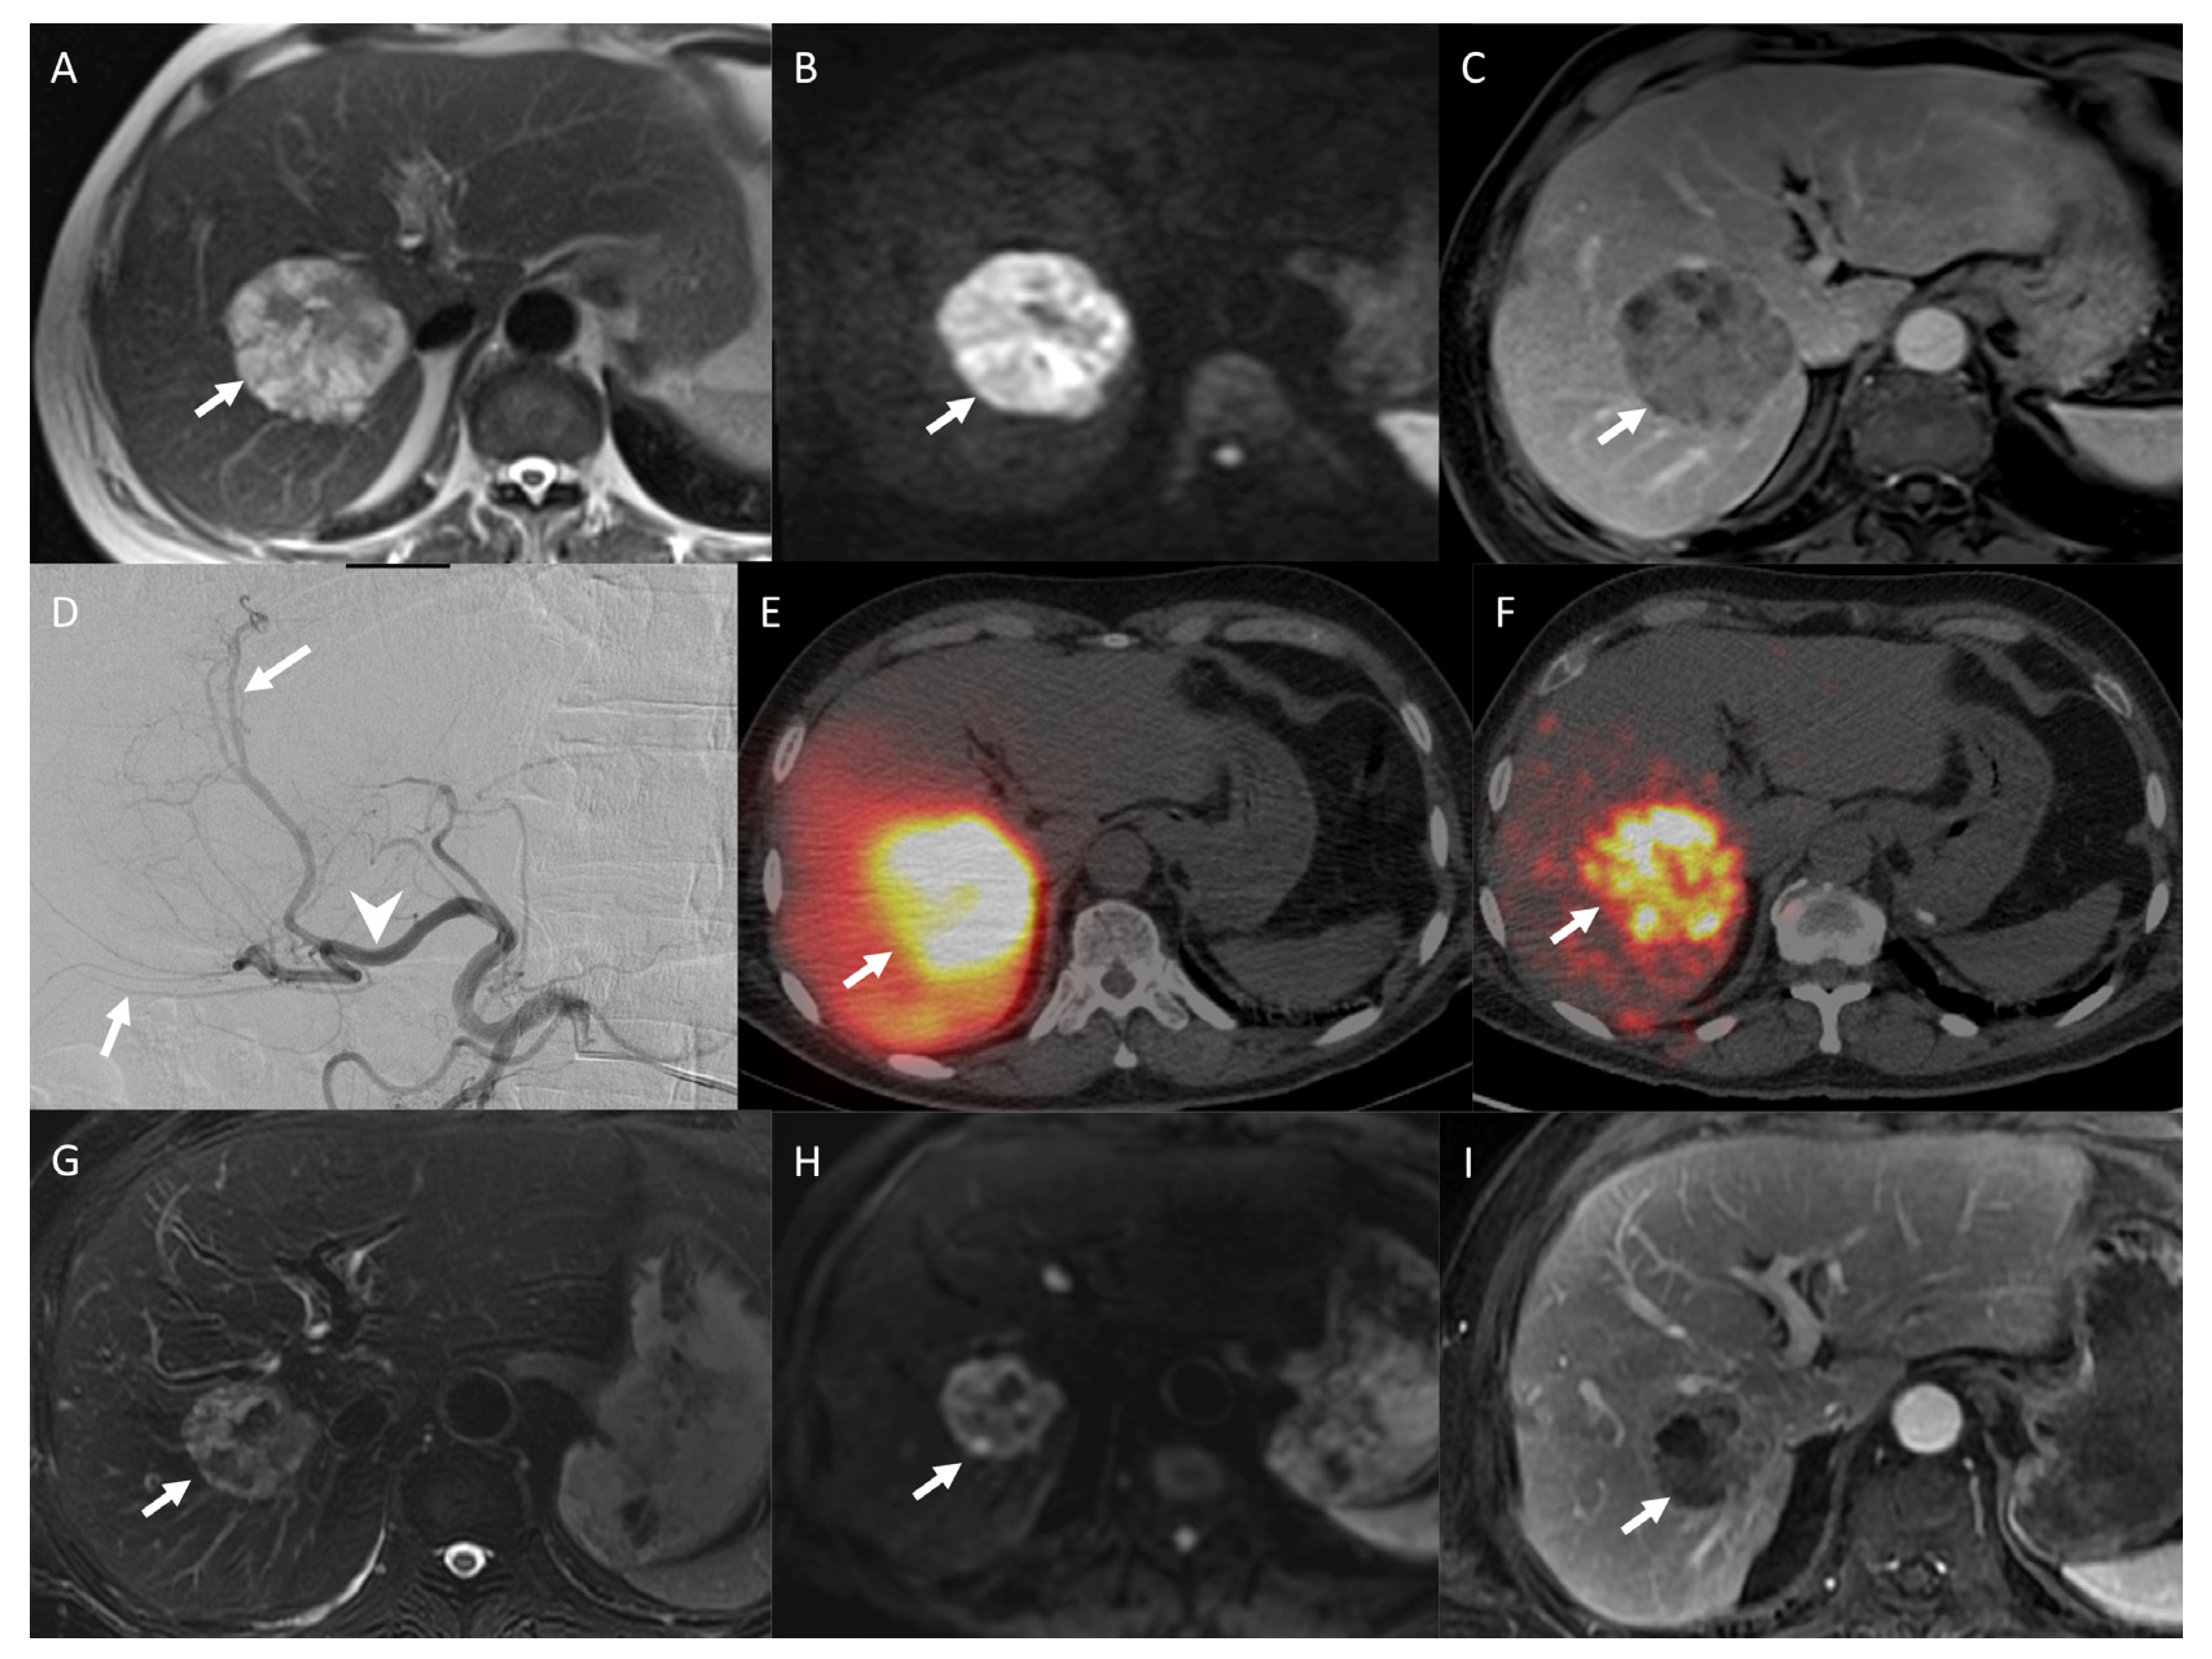

2.8.4. Pre- and Post-Treatment Imaging Prognostic Factors

3.2. How to Perform a SIRT

3.5.2. Disease Control and Radiological Response

3.6.2. Post-Therapeutic Imaging Prognosis Factors